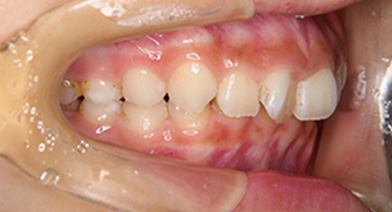

- 治療前 治療後

治療前(横)

| 症例タイトル | 過蓋咬合 |

| 治療内容 | かみ合わせが深く、下顎が後方におしこめられているケースになります。 まず、バイトプレートによるかみ合わせの高さ、下顎の前方適応のコントロールをした後、ワイヤーを装着しました。 下顎の前方適応が難しいケースは、上顎の大臼歯の遠心移動が必要なこともあります。 |

| 患者さまの年齢 | 10代 |

| 患者さまの性別 | 女性 |

| 治療期間 | 1年4ヶ月 |